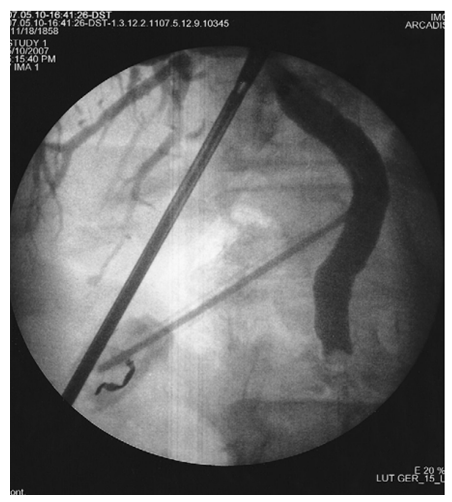

As can be seen from the table above, laparoscopic cholecystectomy was performed in 34 (56.6%) cases in patients with ACP; Laparoscopic cholecystectomy with assisted EPST using the Rendezvouz technique (LERV) – in 11 (20%) cases, and EPST and Laparoscopic cholecystectomy – in 7 (12.7%) cases with ACP combined with choledocholithiasis. In 10 (16%) cases of ACP in patients with concomitant somatic diseases and in elderly and senile patients, puncture interventions with drainage of the gallbladder under visual ultrasound control were performed at the first stage, followed by laparoscopic cholecystectomy at the second stage after improvement of the general condition of patients and indicators of endotoxemia, as well as adequate preoperative preparation, Of these, 4 have EPST supplemented at the 2nd stage.When performing LERV in patients of the first group (11 patients), the gallbladder was removed laparoscopically and the common bile duct was sanitized by endoscopic access through the Large duodenal papilla (LDP). At the first stage, after the cystic artery was isolated, it was clipped with a 5 mm titanium clip and crossed using an U-shaped hook using monopolar cutting. Next, the cystic duct was isolated at its maximum extent. After applying a 5 mm titanium clip to the cystic duct in its distal part, closer to the neck of the gallbladder, an incision of the cystic duct was performed below the applied clip to perform intraoperative direct cholangiography (Fig. 1, 2).  | Figure 1. Intraoperative cholangiography using forceps |

| Figure 2. Intraoperative cholangiography |

During the second stage of surgery (Rendezvous), joint work of surgical and endoscopic teams is necessary. The surgeon performed an incision of the cystic duct just below the previously applied clip and inserted a 0.035 Fr endoscopic string 450 cm long into the cystic duct through a 3 mm diameter trocar. Then he conducted it antegradely through the LDP into the lumen of the duodenum. After the string was passed through the LDP, the endoscopist conducted a video duodenoscope in the duodenum in the usual way and visualized the LDP in the lumen of which the string was located. From the side of the lumen of the duodenum, the string was captured with a modified hollow endoscopic bougie (Fig. 3).At the third endoscopic stage of the hybrid surgical intervention, the papillot was lowered along the string and inserted into an ampoule of LDP, thus performing selective intubation of the choledochus. Retrograde endoscopic papillosphincterotomy (EPST) was performed using the standard method (Fig. 4).Then the papilloma was removed, leaving an endoscopic string in the biliary tract. Depending on the diameter of the common bile duct and the size of the stones, lithoextraction was performed with four-string Dormia baskets of various sizes and stiffness (Fig. 5).  | Figure 3. Capturing the string in the lumen of the duodenum |